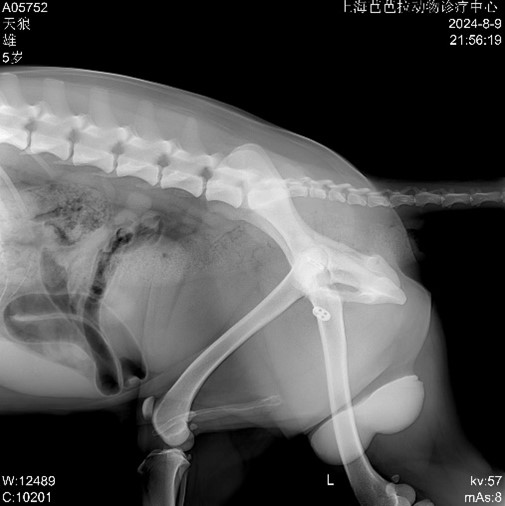

▼ Post-op Imaging